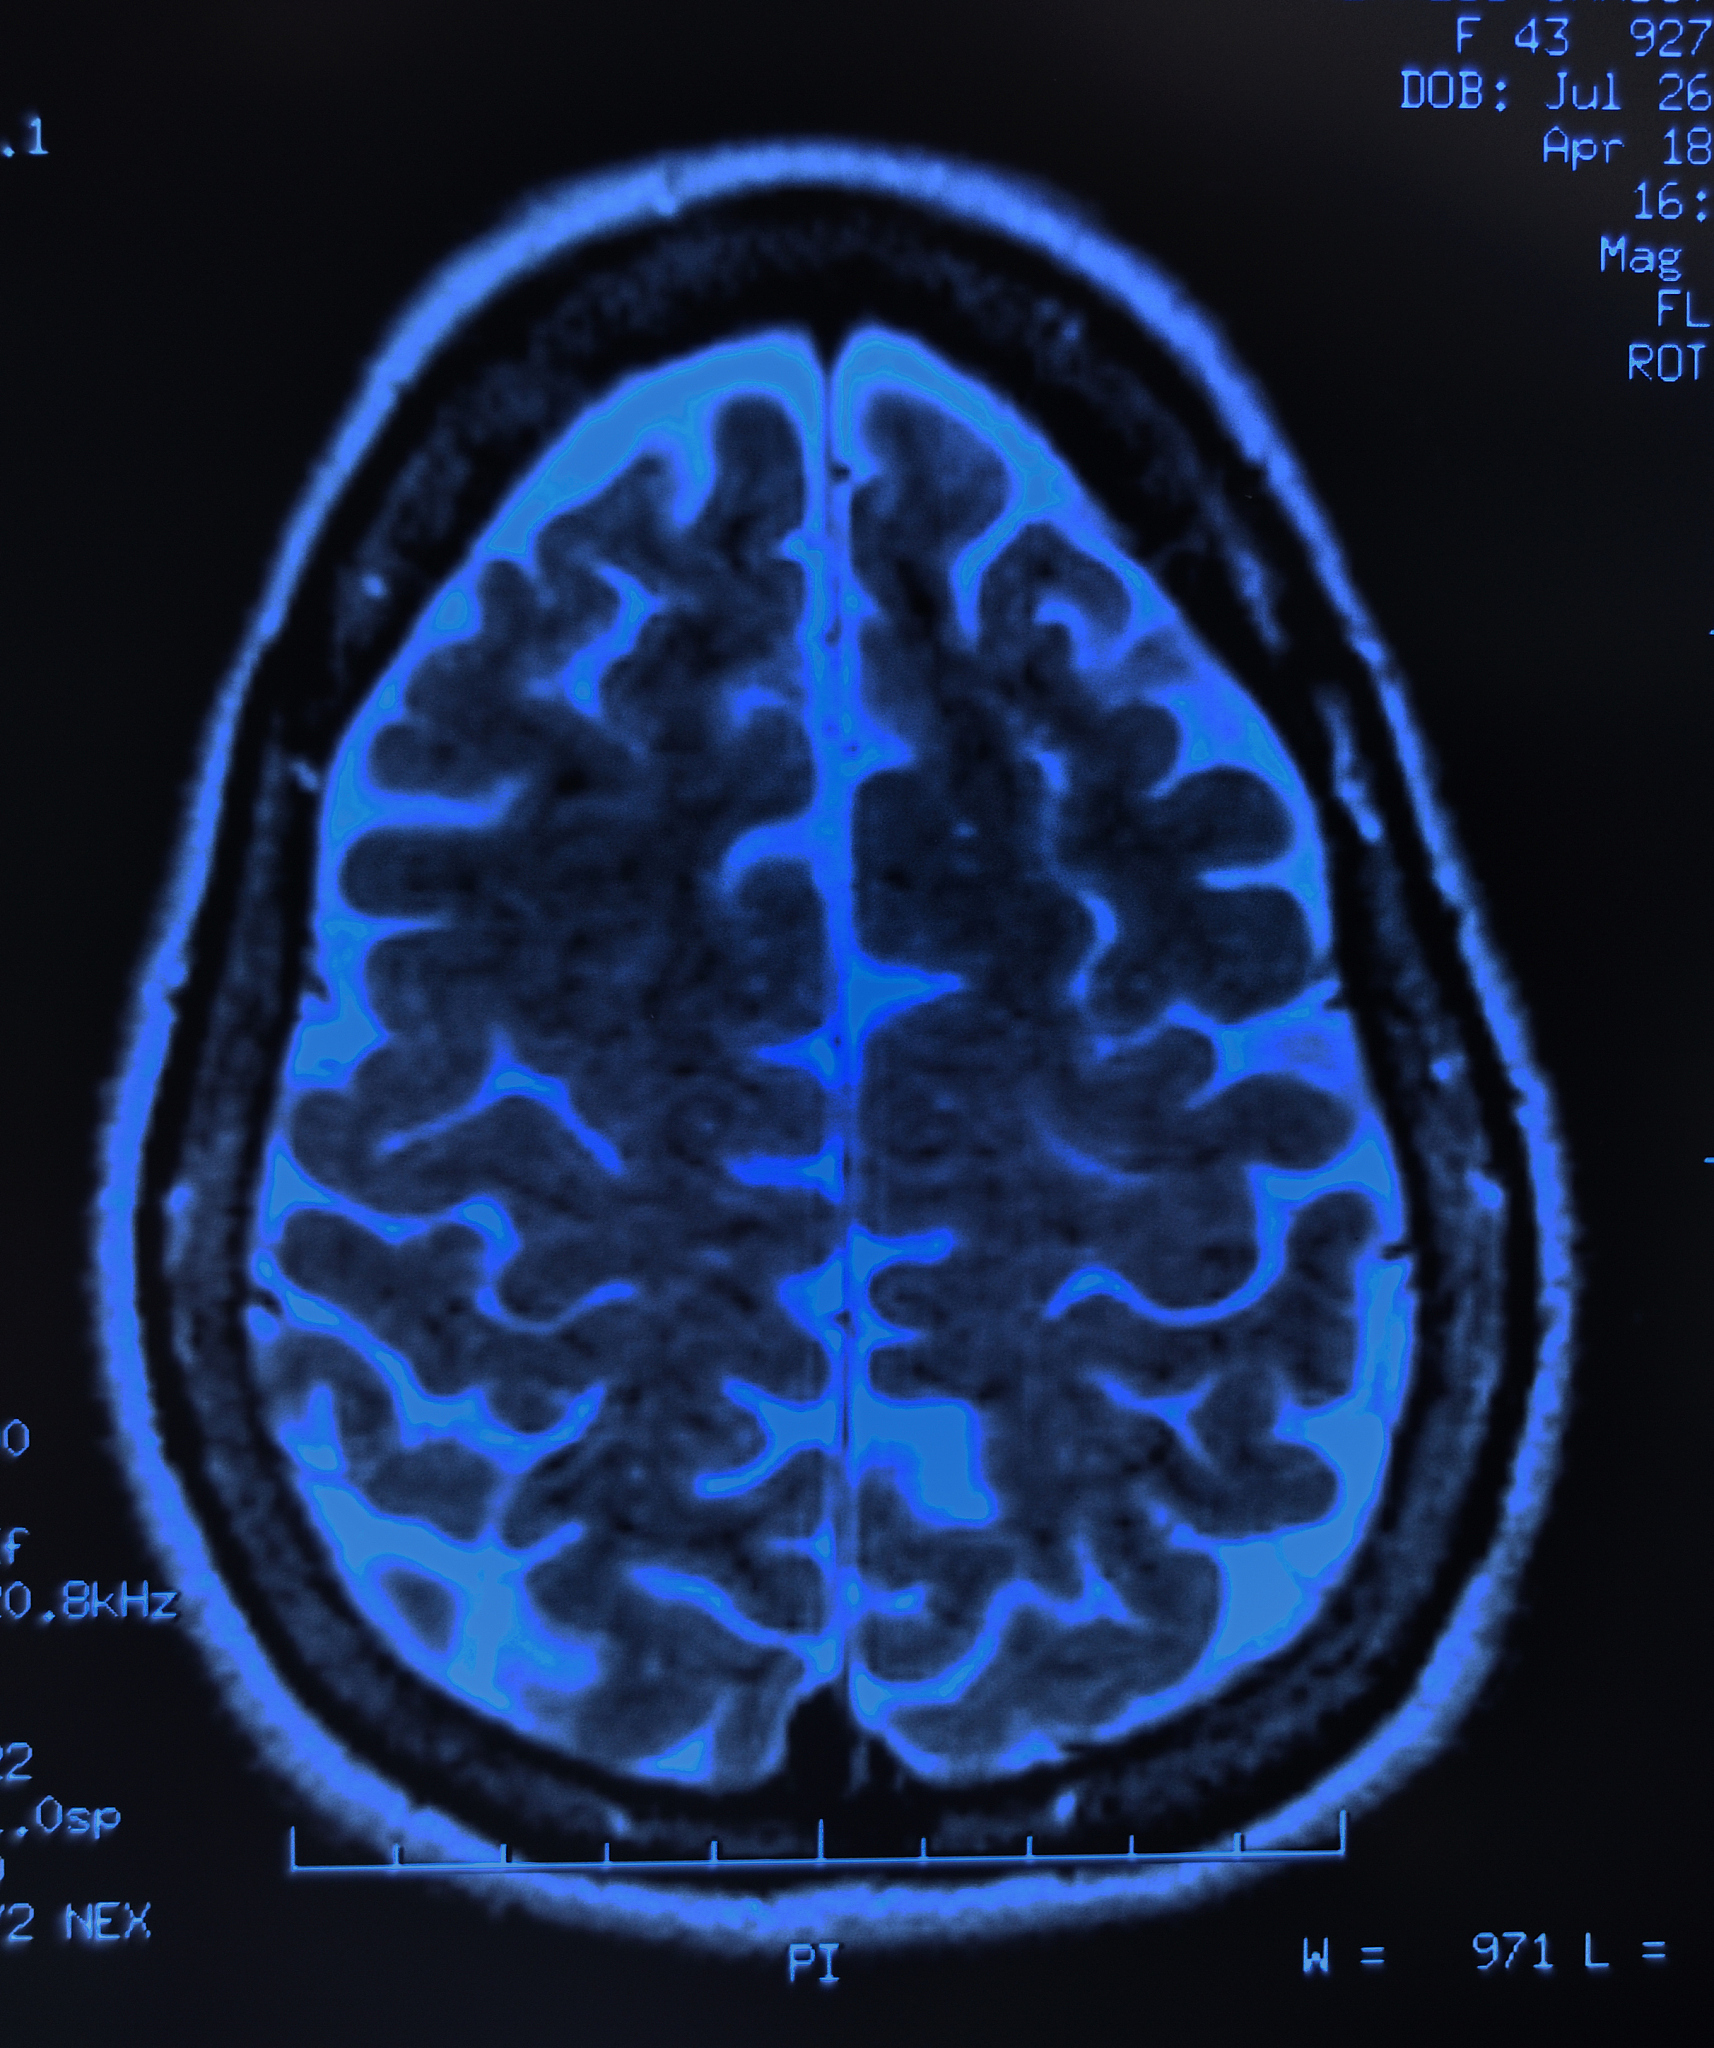

快速识别中风原因对于患者的治疗和预后至关重要。影像学技术,如磁共振成像 (MRI) 和计算机断层扫描 (CT),能够提供大脑的详细图像,帮助医生确定中风的类型、位置和严重程度。

通过快速识别中风原因,医生可以采取更有针对性的治疗方案,例如溶栓治疗或血管内介入治疗,以最大程度地减少脑损伤并改善患者的预后。

因此,利用影像学技术快速识别中风原因具有重大意义,这对于优化患者治疗策略和改善长期健康状况至关重要。